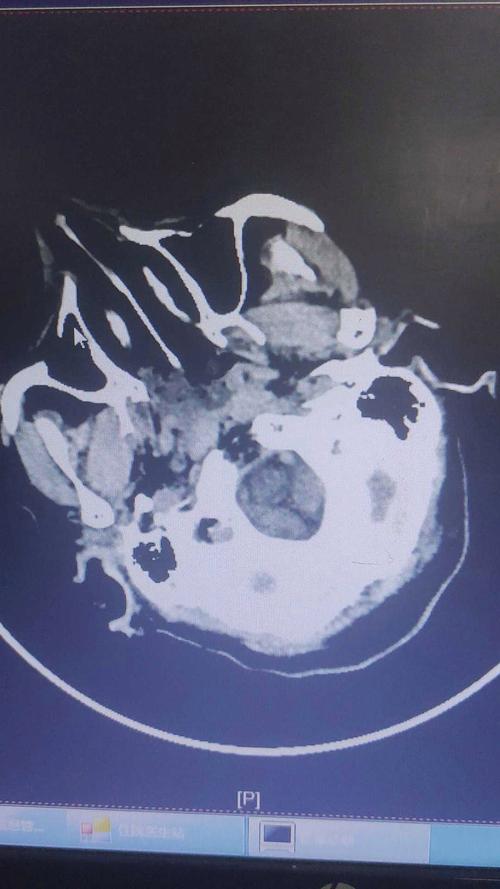

(图片来源网络,侵删)